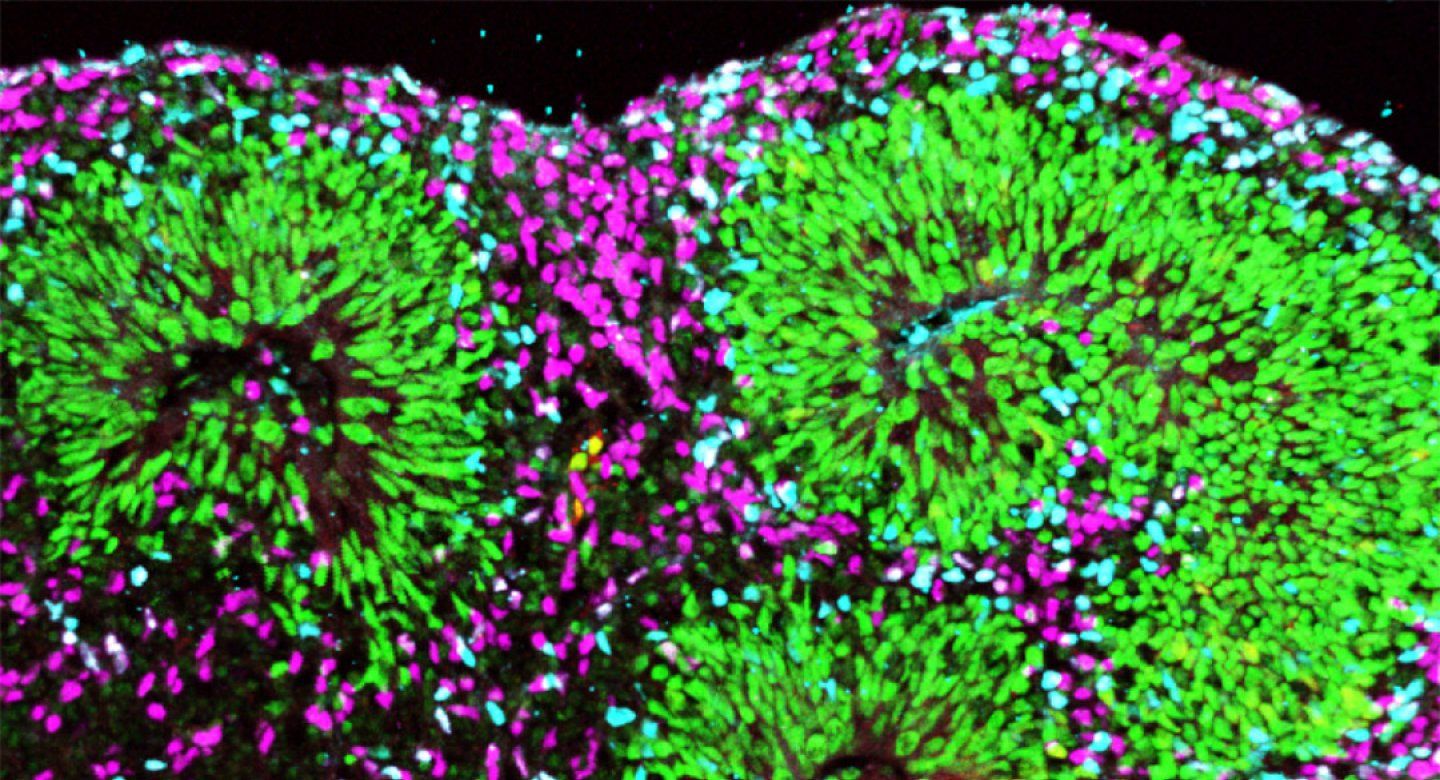

Коннектом мозга: визуализация связей и нейронных путей